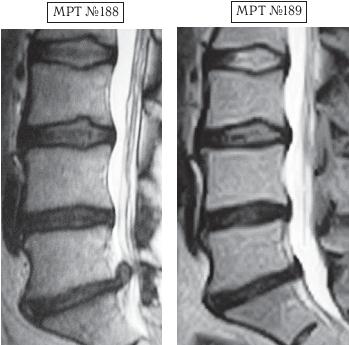

МРТ № 4

МРТ № 5

На МРТ № 4 наблюдается межпозвонковый диск в начальной стадии развития дегенеративно-дистрофического процесса.

На МРТ № 5 наблюдается межпозвонковый диск на более поздней стадии развития дегенеративно-дистрофического процесса.